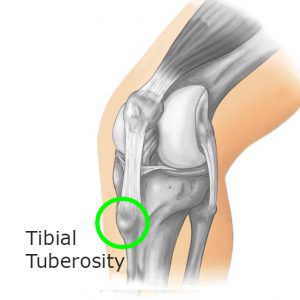

È dovuta a una infiammazione della cartilagine di accrescimento della apofisi tibiale anteriore o osteocondrosi, dove si inserisce il tendine rotuleo.

- alla palpazione della tuberosità

La presenza clinica di una tumefazione al di sotto della rotula e radiologicamente una frammentazione del nucleo di accrescimento stesso sono diagnostici della malattia.

Attraverso una radiografia è possibile anche individuare una eventuale frammentazione della apofisi tibiale.